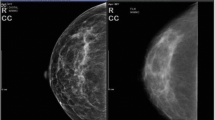

Authors in [3] did a review, based on several articles from 2002 to 2010, which reveals Screen-film mammography (SFM) limitations, which are illustrated by its false-negative rate ranges from 4 to 34%. Even if, mammography has been considered for long time as the gold standard for breast cancer screening and detection, the need of new techniques to overcome those limitations came in evidence. Also publication [4] has presented near-infrared fluorescent (NIRF) as key roles in clinical diagnosis, as well as evaluation of disease status and treatment of tumour. However, it is very important for the image processing to have a Clair strong NIRF signal, so that the image taken, can content a lot of information very near to the real state of the breast. As we know, as early is the detection of the tumor, as better and successful is the treatment. In addition, authors [5] talked about the difficulty to obtain tumor parameters such as: metabolic heat, tumor depth and diameter from a thermogram, Furthermore, another paper [6] mentioned the limitations of computed tomography (CT) and magnetic resonance imaging (MRI), which have a low sensitivity for sub-centimetre lesions due to their limited spatial resolution. In addition, [7] mentioned another bad point of a successive mammography test for a period of 10 years, according to his study paper, the rate of false positive diagnosis for women after doing a mammogram every year for 10 years is 49.1%. Other aspect has been explored in [8], where he advised to do (Sentinel Lymph Node) SLN biopsy, in order to reduce the a higher risk of disease (breast cancer) progression, in addition authors [9] has advised, to not take breast cancer’s thermography result like sufficient information for decision taking.

Paper [3] deal with pre-digital mammography (FFDM) and digital infrared thermal imaging (DITI) as imaging modalities that would overcome mammography limitations. Due to its ability to selectively optimize contrast in areas of dense parenchyma, Digital mammography is superior to screen-film mammography in younger women with dense breasts, however we observe due to the density of their breast tissue, a lower sensitivity of mammography. In Other hand, the utilization of Digital Infrared Imaging is based on the principle that, metabolic activity and vascular circulation in both pre-cancerous tissue and the area surrounding a developing cancer, is almost always higher than in normal tissue, also it is reported that the results of thermography can be correct 8–10 years before mammography can detect a mass in the patient’s body. In addition of that, a shortage of qualified radiologists, also causes an urgent demand for the development of computer technologies as computerized thermal imaging (CTI).